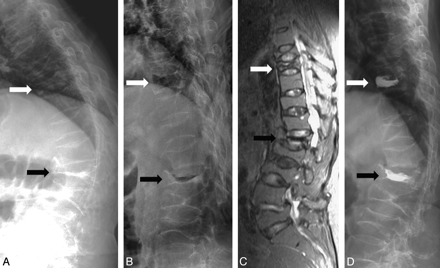

Toyone et al8 used supine and standing radiographs, and McKiernan et al1 used standing and supine (with or without bolster) radiographs to demonstrate mobility. In the study of McKiernan et al, dynamic fracture mobility was demonstrated in only 44% of patients, but they did not use a bolster in supine lateral radiographs in all patients. The vertebral body height is taller in supine with bolster radiographs (Fig 1B, white arrow) than in supine-only radiographs (Fig 1C, white arrow). In the study of McKiernan et al, 23 mobile fractures all showed marked mobility and the average anterior vertebral height increased 106% compared with the initial fracture height.1 No case of mild mobility was noted in their study. However, in another study by McKiernan et al,9 they demonstrated latent mobility of osteoporotic VCFs that was not obvious in their current standing and supine lateral radiographs. This means that mild mobility cannot be demonstrated in standing and supine lateral radiographs. To get the best comparison effect, we modified this technique and used sitting (instead of standing) and supine cross-table with bolster lateral radiographs in every patient. Although 99% of our patients showed dynamic mobility, 24 patients showed only mild mobility (Fig 2, white arrow). The mild mobility in these patients may be not obvious in standing and supine radiographs. If the patients with mildly mobile VCFs are excluded, then the percentage drops to 76.2%.

A 69-year-old woman with severe back pain due to T9 and L1 compression fractures. A and B, Sitting (A) and supine with bolster (B) lateral radiographs show mobility at T9 (white arrow) and L1 (black arrow). C, Sagittal STIR MR image demonstrates hyperintensity at T9 but hypointensity at L1. D, Postvertebroplasty lateral radiograph shows cement filling in T9 and L1.